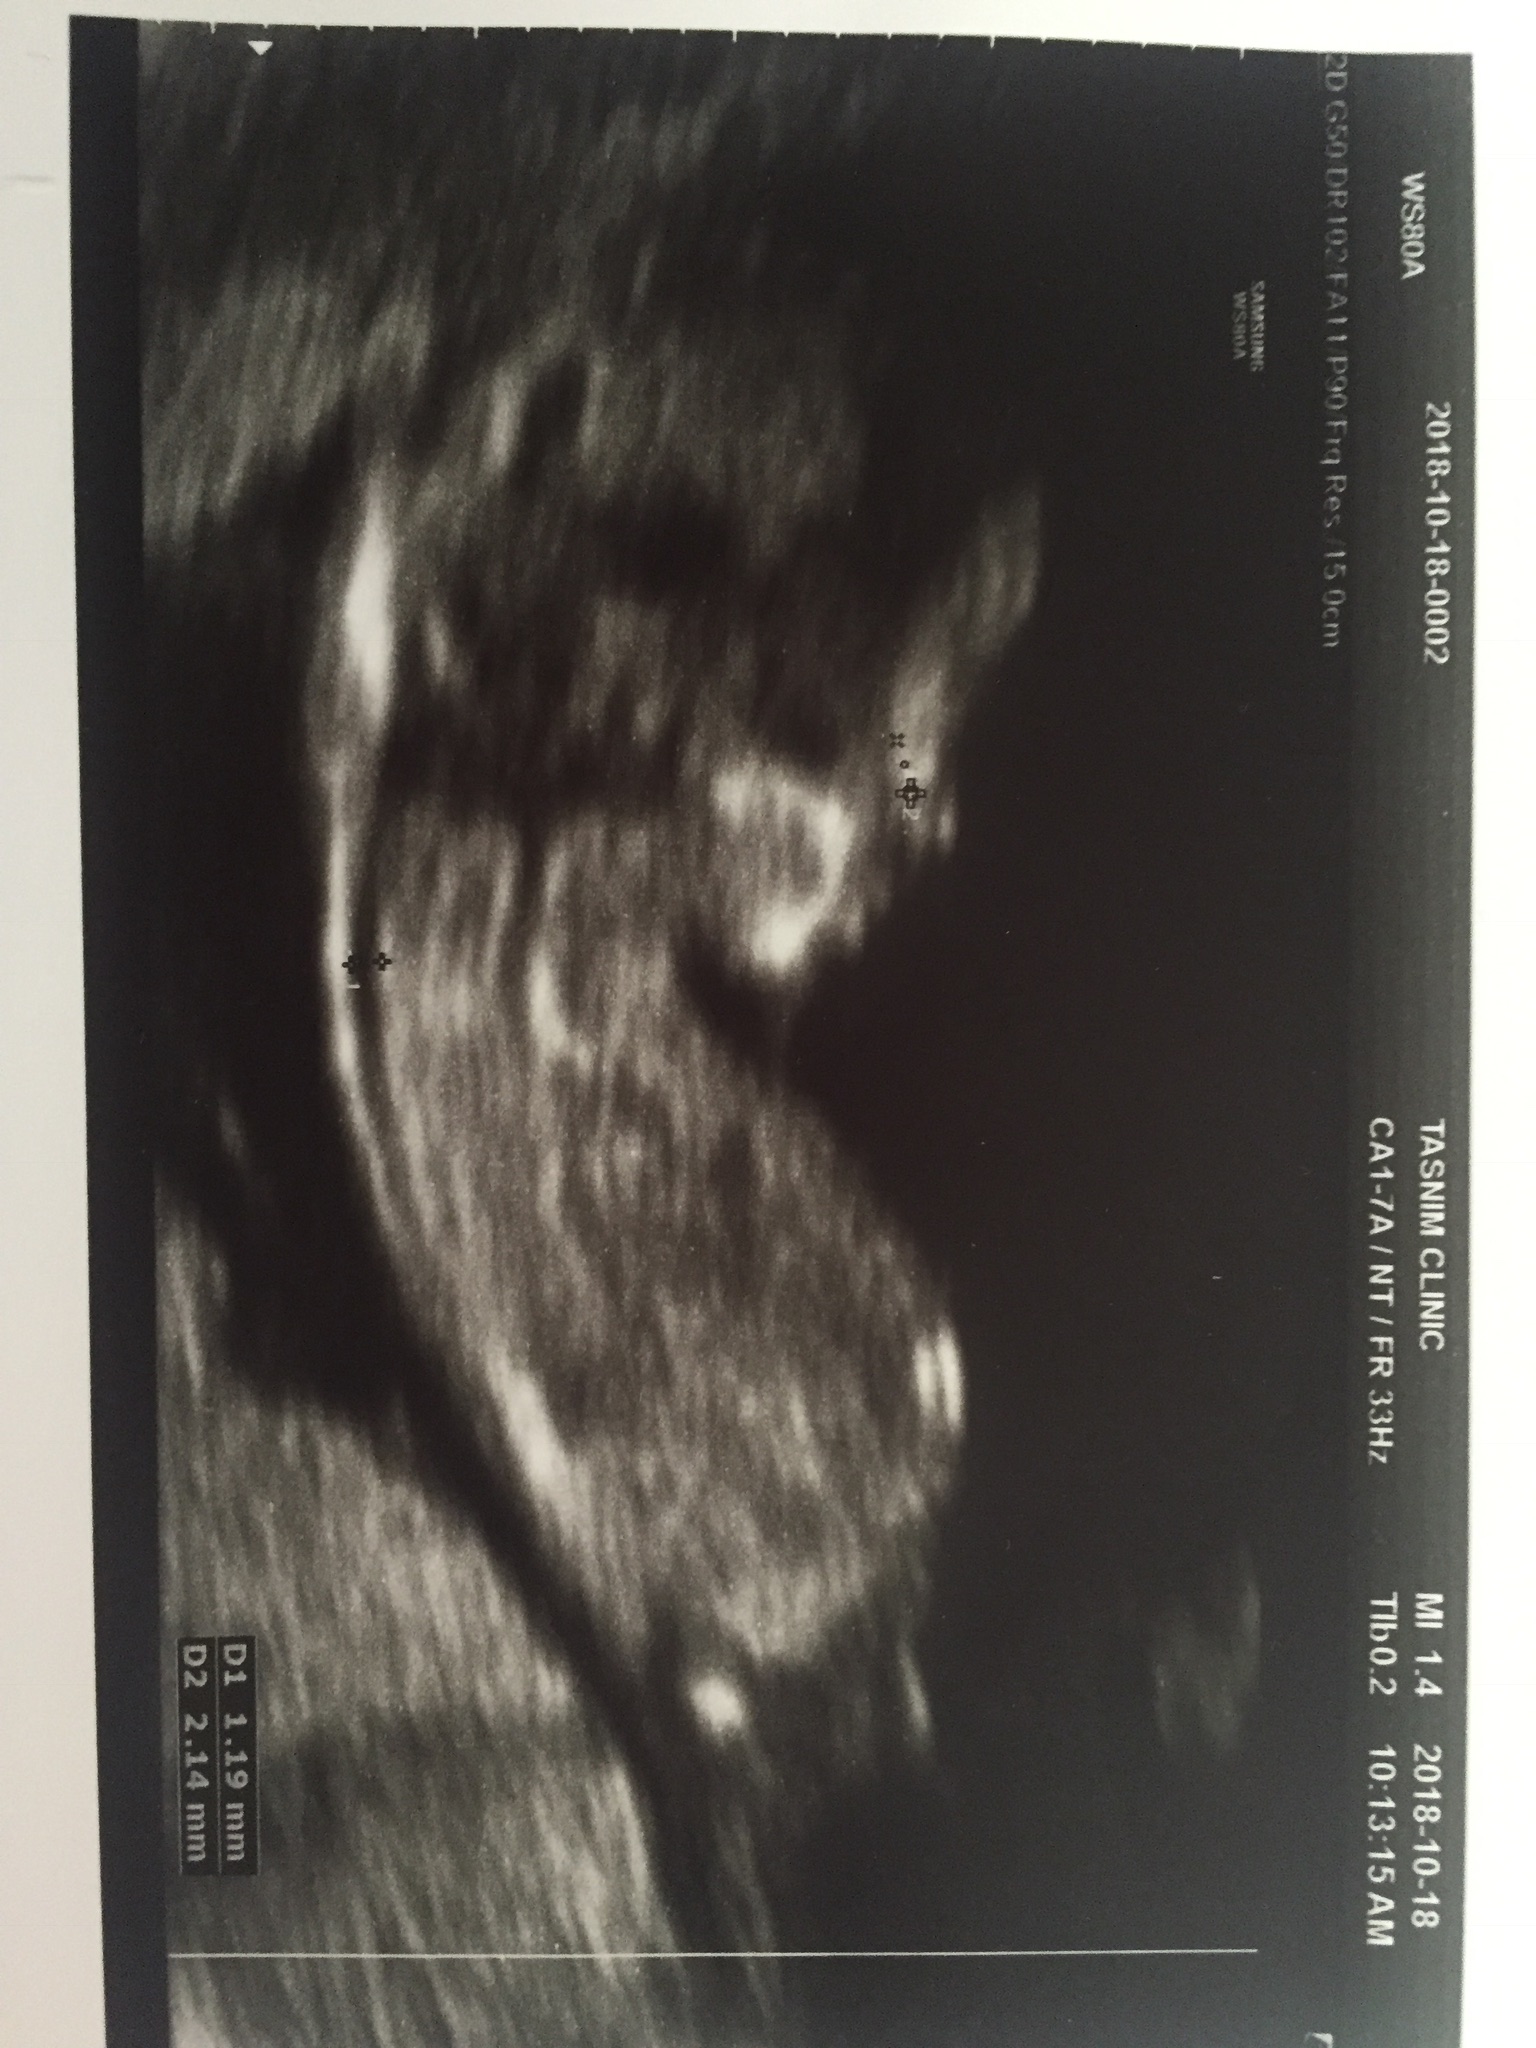

عطیه۱۲ عضویت: 1397/05/24 تعداد پست: 744 سلام عزیزم،اول از همه تبریک میگم بت انشالله بارداری خوبی داشته باشیمن از سونو ۸ هفته ام عکس ندارم این عکس سونو ۱۲ هفتمه

zemastooon عضویت: 1397/06/31 تعداد پست: 2024 سلام عزیزم،اول از همه تبریک میگم بت انشالله بارداری خوبی داشته باشی من از سونو ۸ هفته ام عکس ندارم ... ابجی من 12 هفته ک رفتم اصلت واضح نیست معلوم نیست چیه خداجونم شکرت هزار بار شکرت بابت نی نی،، باارزش ترین هدیه رودادی.انشالله همه ی منتظرا دامنشون سبز شه آمین

عطیه۱۲ عضویت: 1397/05/24 تعداد پست: 744 ابجی من 12 هفته ک رفتم اصلت واضح نیست معلوم نیست چیه ینی خودتم اون موقع ک سونو میکرد هیچی ندیدی؟واضح نبود؟مال من واضح واضح بود نی نیم داشت انگشتشو میخورد